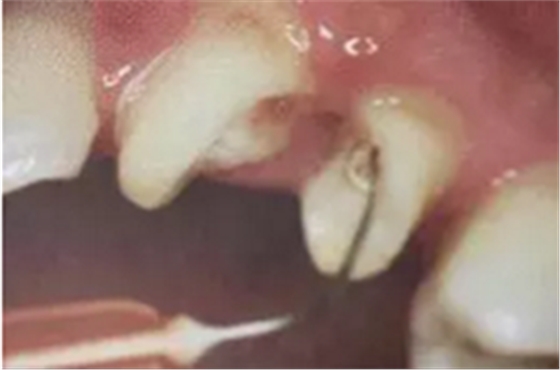

6. 纖維樁的試放和裁戴

纖維樁試放時(shí)應(yīng)用鑷子夾持將其插入預(yù)備的根管樁道中(這涉及無菌觀念和操作),就位時(shí)無阻力可稍有錮住感。

(鑷子夾持(正確))

(污染手套夾持(錯(cuò)誤))

(技工鉗裁剪(錯(cuò)誤))

試放后應(yīng)按所需長度用細(xì)粒金剛砂車針切割裁剪。

(粘樁堆核固化后裁剪)

為防止裁剪過程中有可能造成樁表面的污染,可以粘結(jié)固位后再進(jìn)行裁剪。

操作時(shí)。光固化燈應(yīng)在樹脂核成形后,頰、舌、合面分別光照20秒,在完成預(yù)備體后將其磨除。